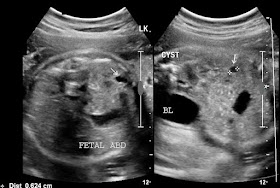

Solitary cyst of fetal kidney:

This 2nd trimester fetus shows a solitary cyst of the lower pole of left fetal kidney. The cyst is small (6 mm.) with no internal debris or septae. The fetal renal cyst shows no communication withe the pelvicalyces which appear norma, thus ruling out fetal hydronephrosis. The fetal urinary bladder (BL) appears normal. The above ultrasound images are typical of uncomplicated cyst of the fetal left kidney. The important differential diagnoses in this case include renal abscess or renal hematoma, both of which seem improbable here. The other possibility is that this cyst is precursor to onset of autosomal dominant polycystic kidney disease (adult type). Polycystic kidney disease may develop in this baby during adult life. Both images are courtesy of Dr. Ravi Kadasne, MD, UAE.